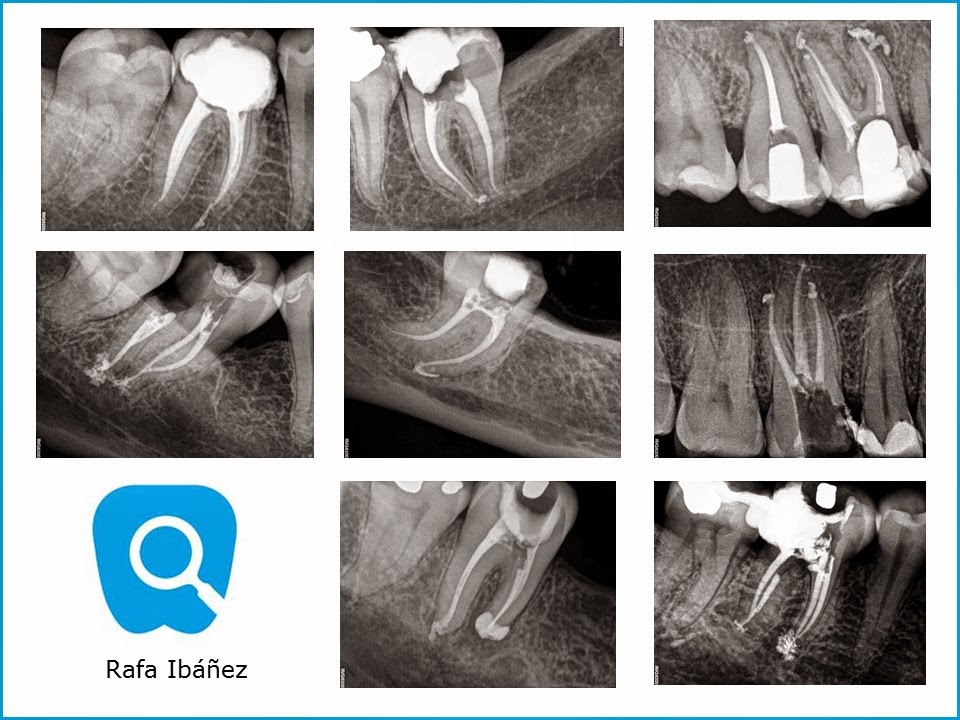

Algunos casos de molares...

Algunos casos de molares superiores e inferiores. Desde el blog, agradecer a los compañeros que nos derivan pacientes para realizar diversos tratamientos de endodoncia.